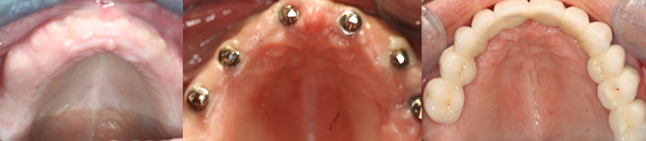

FULL ARCH DENTAL IMPLANT

Extensively damaged or missing teeth can not only impede you from living a fulfilling life but can also affect your health and confidence. But full arch mouth reconstruction solution, using implants can be used to support ill-fitting dentures or restore the entire arch with a bridge to improve appearance and reinstate complete oral functions.

4-6 implants are placed in each jaw an aesthetic, functional bridge is fabricated over the implants. It need not be removed to clean on a daily basis and is probably the closest to natural teeth in function and aesthetics.

2-4 implants are placed in the lower jaw, 4-6 implants in the upper jaw can support a full denture. This procedure is very economical, greatly improves retention, stability and function. All of these stages can be carried out in the single appointment depending on need and condition of the patient.

IMPLANT SUPPORTED BRIDGE

Card image Actual Practice Photographs ©Dr.Pavan Bopanna

IMPLANT SUPPORTED DENTURE